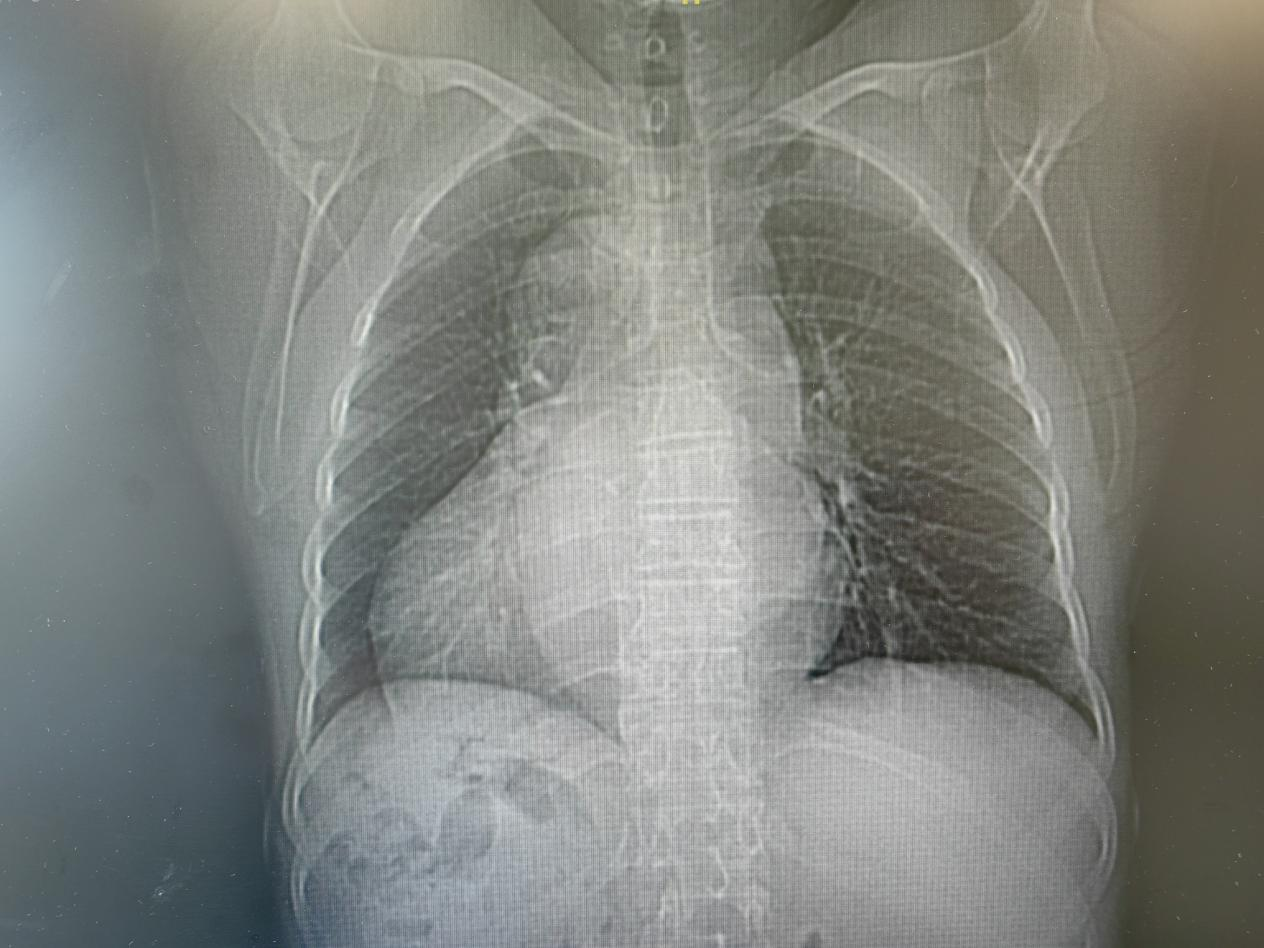

2025-09-18福建日报 | 心脏长反还乱跳 厦心微创脉冲技术为罕见“右心人”精准消融 -